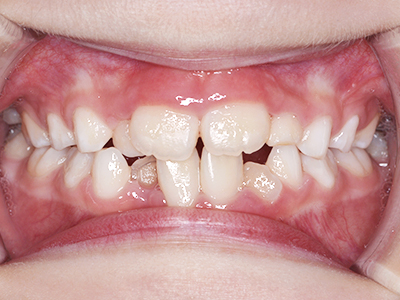

小児矯正について

歯並びの相談に来られるお子様は、口呼吸をしているケースが多く、これが歯並びに大きな影響を与えています。

↓ - さまざまな不正咬合が生じる

ないき歯科クリニックでは、上あごの成長不足を補い、鼻呼吸を獲得しつつ歯列を整え、将来のお口をより健康な状態にすることをゴールに定める矯正治療をおこなっています。